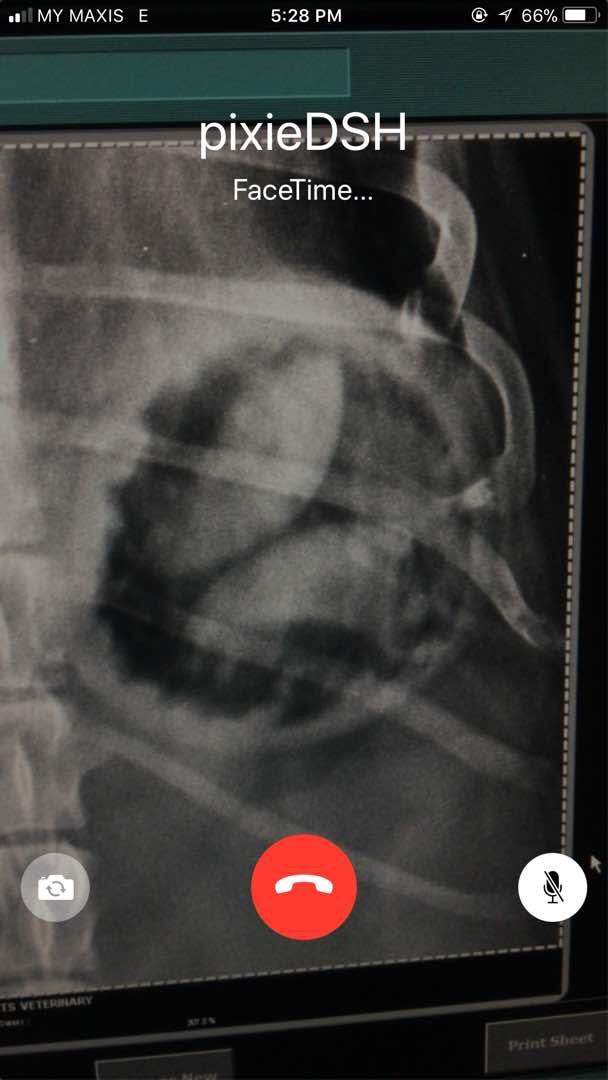

My 7-year old male dachshund is having bloody stool for the last 2 days, today went for X-ray and the vet couldn't indicate what is in his stomach and whether is a serious matter. Sincerely need your precious advice, I'm so worried now.

Hi there and thank you for using pet coach to address your concern. The x-rays that you provided show what looks to be foreign material in the stomach. It looks very similar to pieces of a ball with the rounded edges. This does not appear to be ingested food based on the appearance and shape period while not serious at the moment, one of these could pass from the stomach into the intestines and cause serious problems. I would consider rechecking the X-ray a few hours after the previous x-rays have been taken to see if there has been any change in the pattern. If there is no change in the pattern, I would suggest taking pixie in for surgery to have the abdomen explored. Prior to the surgery, you can also have an abdominal ultrasound performed to help confirm foreign material in the stomach. I hope this helps guide you in the right direction. Please feel free to contact you any other questions or concerns you may have